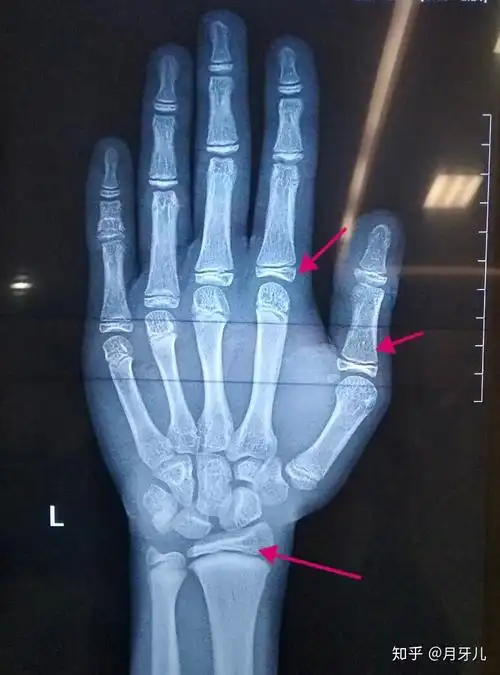

帮忙看下我骨骺线闭合了嘛去年11月拍的好几个月没长了今年16

男孩,年龄17岁,去医院测骨密度拍了x光片(如图),请看看骨骼线是否闭合